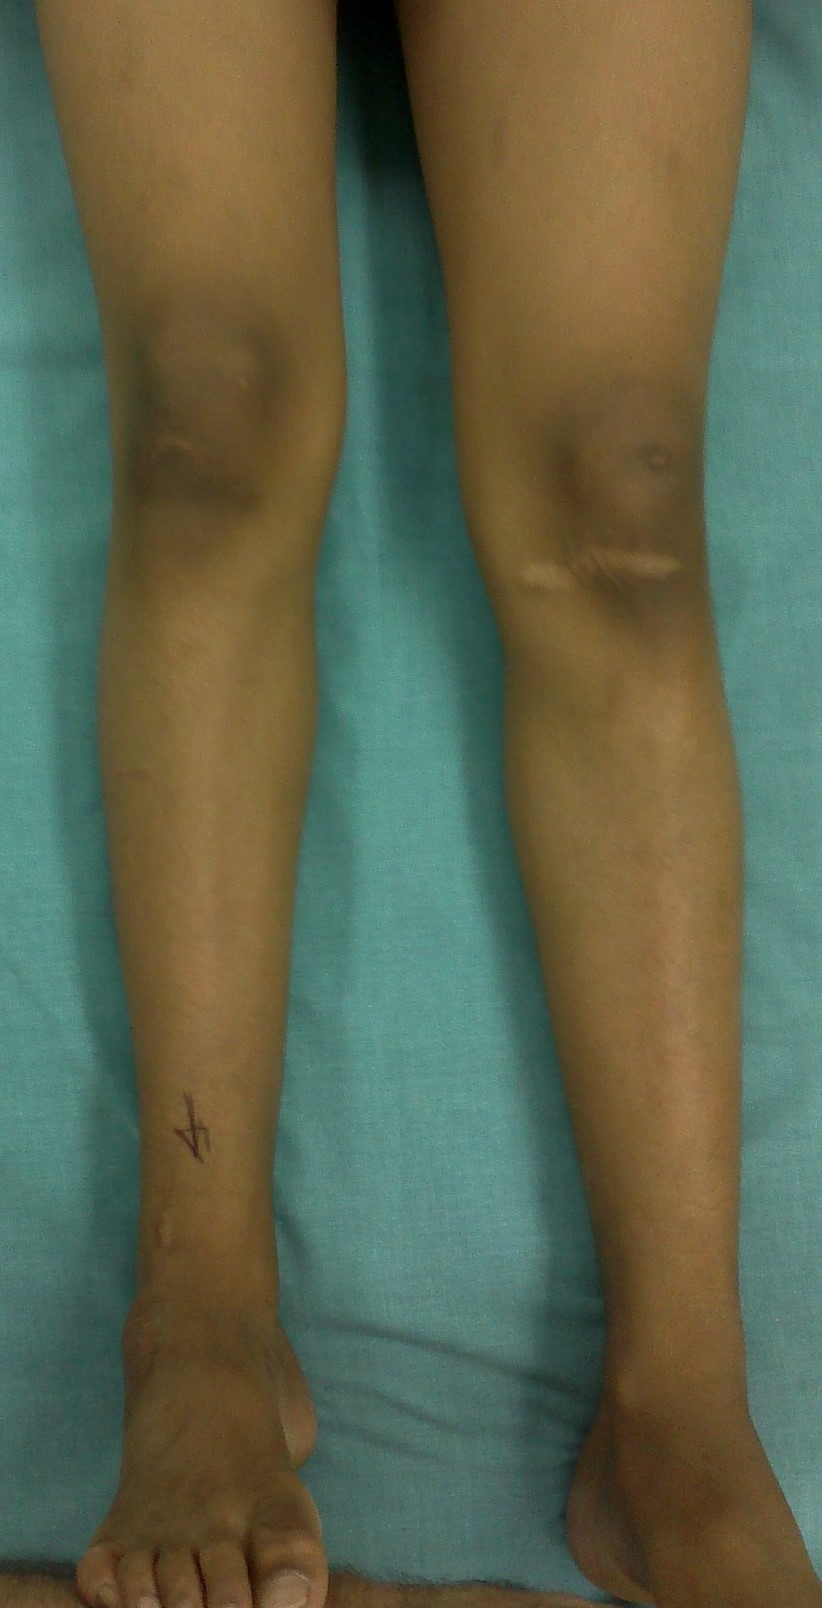

Leg length discrepancy (LLD) results from congenital, developmental, posttraumatic, or post-surgical causes.

Treatment goals are correction of LLD with associated deformity while preserving function of muscles and joints and restoring normal alignment of the limb.